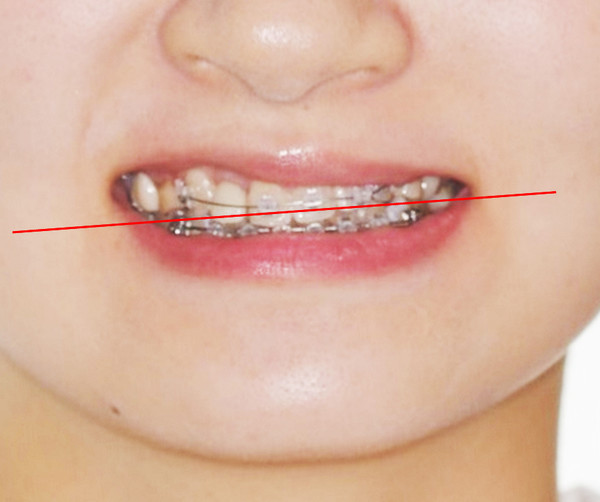

Occlusal canting을 수정하기 위해 상악 좌측 임플란트보철물에 bracket을 기울여 붙여서 slot의 방향대로 archwire가 삽입되었을때 좌측 견치는 정출되고 우측 견치는 함입되도록 하였습니다.

Slot의 방향에 맞춰 전치부 occlusalcanting이 개선되었습니다. 좌측견치의 정출이확연히 눈에 띕니다.

초진시부터 마무리까지 양측 견치 tip을 연결한 선을 기준으로 frontal occlusalplane의 변화를 비교 시occlusal canting의 개선을 확인할 수 있습니다.